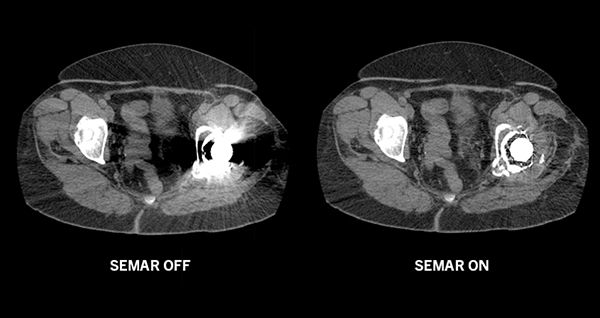

SEMAR™ (Single Energy Metal Artifact Reduction) – технологія зниження артефактів від металу з одним енергетичним рівнем є новітнім доповненням до набору адаптивних діагностичних технологій.

Цей складний алгоритм дозволяє практично виключити металеві артефакти, поліпшуючи візуалізацію імплантів в кістках і прилеглих м'яких тканинах для безпомилкової і впевненої постановки діагнозу.

На відміну від двохенергетичного сканування, Вам не потрібно заздалегідь планувати дослідження, Ви завжди можете зробити реконструкцію із застосуванням технології SEMAR™ після дослідження пацієнта, при необхідності.